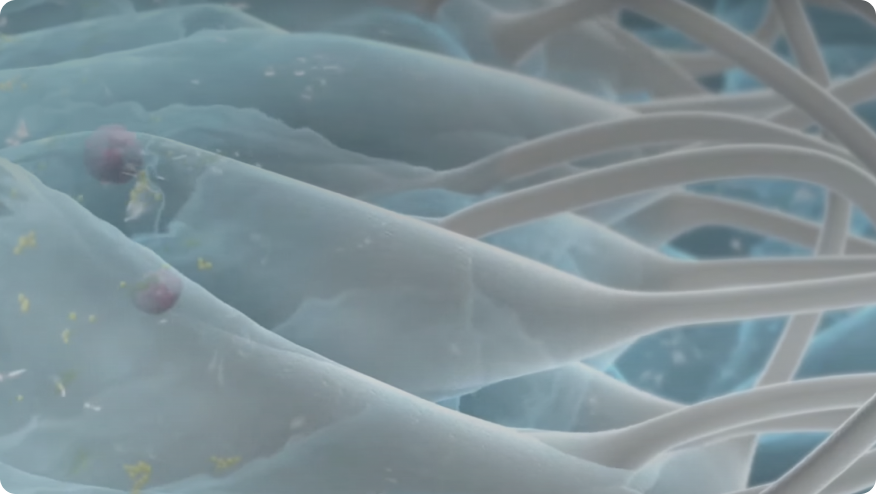

Intimate Contact

Wicking Test

Locks In